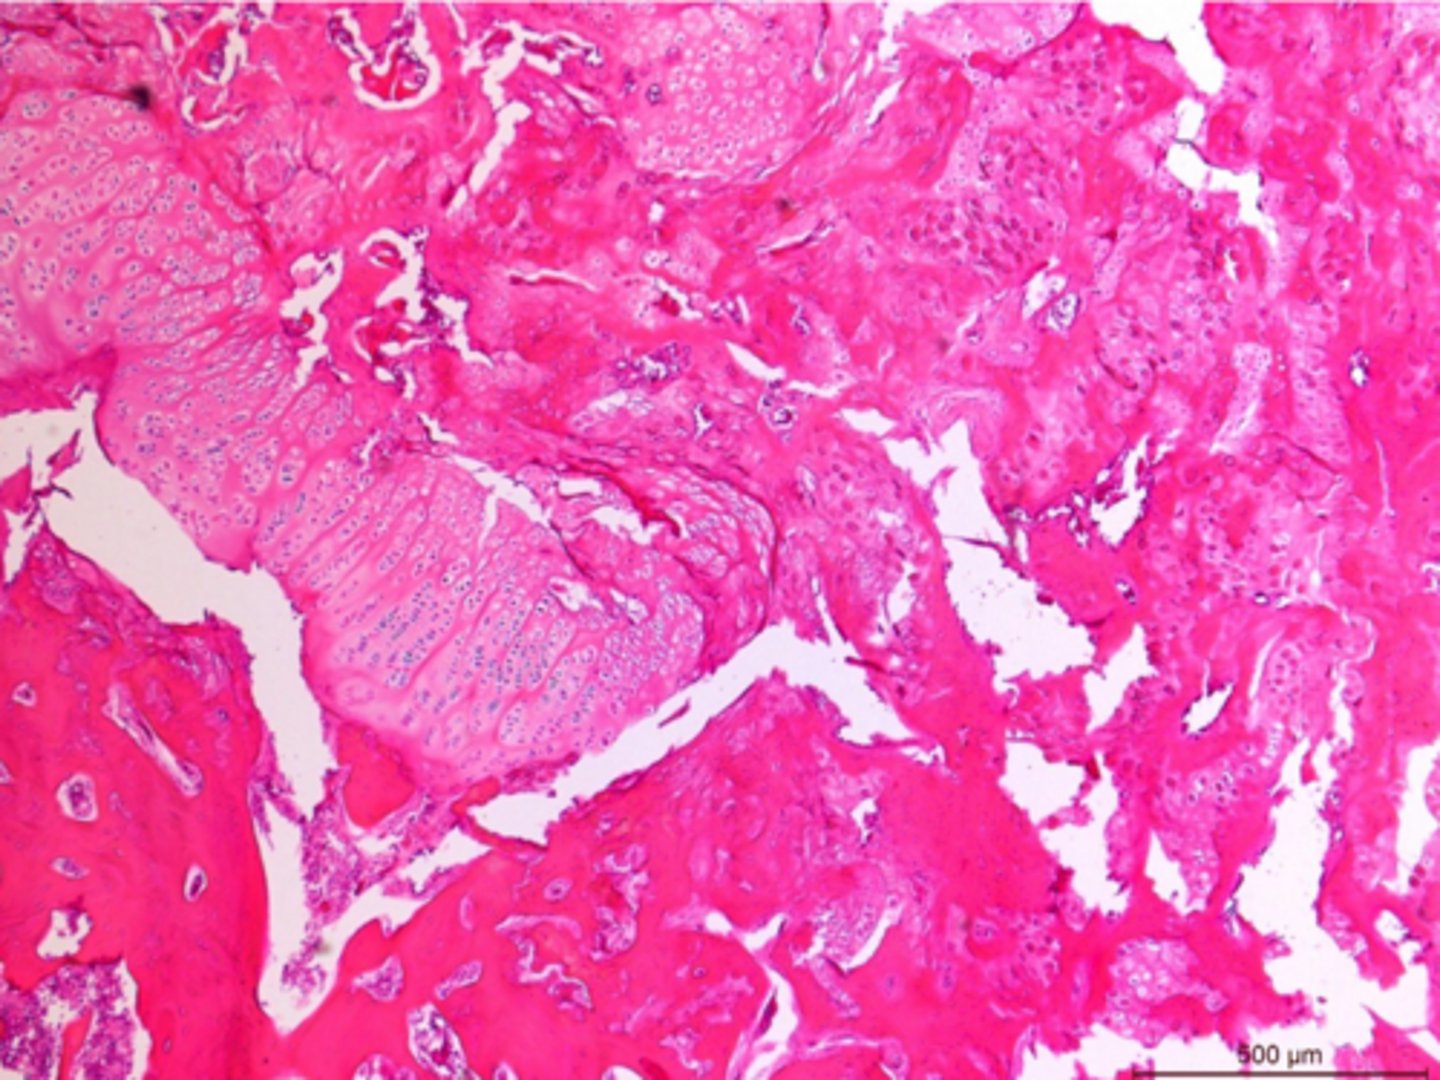

Identify the pathology:

Hypertrophic osteopathy